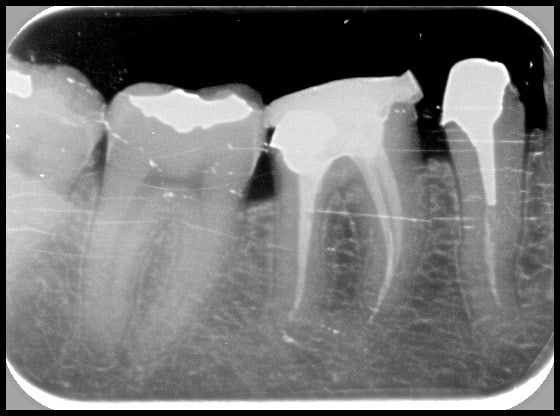

(Des fois l'endo ça marche. Protaper + Gutta condensor)

Reste plus qu'à faire la même sur tous mes cas...

R5 ngbr3g - Eugenol